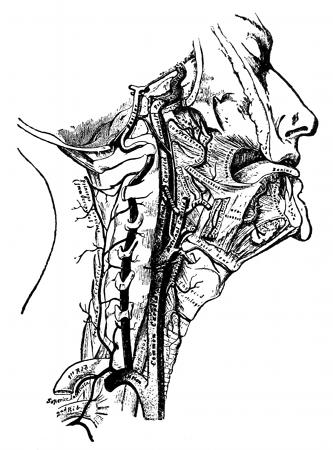

Fig. 3—Lymphatics of the head and neck.

B, the thoracic duct.